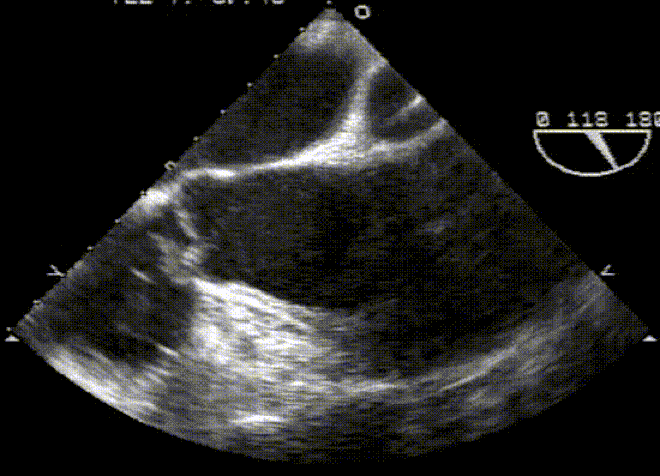

Heart

Limited series of images to reinforce major pathologies